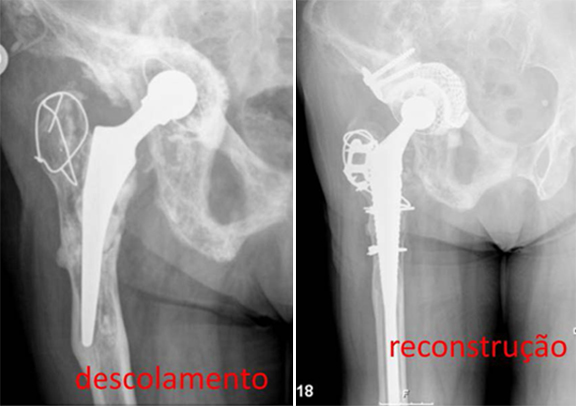

Nos casos de fractura periprotésica, ou seja quando há fractura do fémur ao nível da haste femoral ou logo abaixo da extremidade da haste, a revisão é feita de acordo com as características da fractura.

Geralmente o Rx é suficiente para o diagnóstico.

O grau de dificuldade da revisão está mais relacionado com o tipo da fractura.